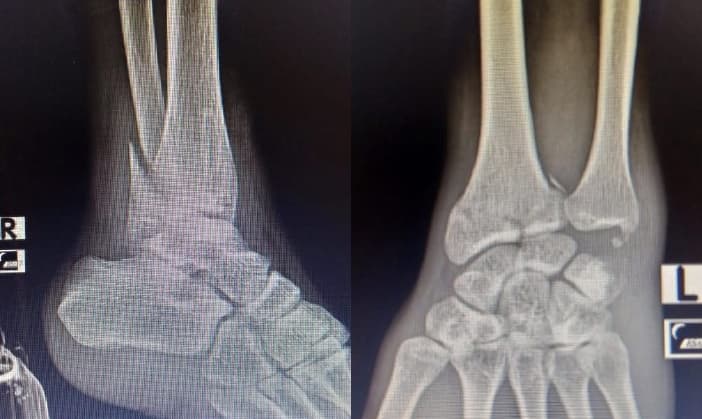

Long story short, saya mengalami kecelakaan motor yang terjadi pada pertengahan 2021 dan mengakibatkan tulang retak di pergelangan kaki kanan dan pergelangan tangan kiri.

Rontgen pergelangan kaki kanan dan pergelangan tangan kiri

Recovery selama 9 bulan lamanya, dimana saat itu saya sulit untuk berjalan dan juga sulit untuk mengetik.

Benar-benar istirahat di rumah, nyalain komputer pun jarang, ngetik pun cuma bisa pake tangan kanan :(

Akhir 2021, kaki dan tangan saya berangsur pulih. Awal 2022 merasa kaki dan tangan saya sudah benar-benar pulih total dan bisa beraktivitas seperti biasanya. Alhamdulillah :)